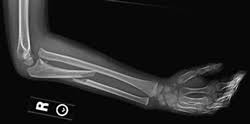

Rx de codo: qué buscar

¿Qué se evalúa en una radiografía de codo AP y lateral? (teórico clínico | poca relevancia)

AP:

Ángulo de carga (valgo fisiológico ~10-15°)

Integridad de epicóndilos

Espacio articular humeroulnar y humeroradial

Cabeza del radio alineada con capítulo (línea radiocapitelar)

Lateral:

Signo de la almohadilla grasa (fat pad sign): grasa desplazada anterior y/o posterior → indica derrame articular → sospechar fractura oculta

Línea radiocapitelar: debe pasar por el centro del capítulo (si no → luxación de cabeza radial)

Olécranon en fosa olecraniana